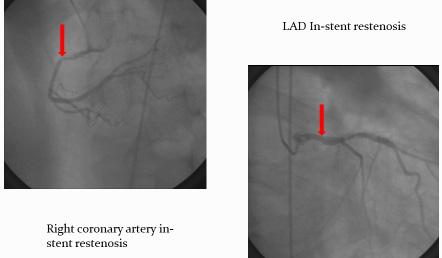

Coronary artery bypass grafting for in-stent restenosis

In the era of stenting, percutaneous coronary interventions are used as initial revas cularization strategy but there is the risk of in-stent restenosis in a significant number of cases. In-stent restenosis is an important clinical problem and those patients are a challenging group for both interventional cardiologists and cardiac surgeons as generally they are patients with aggressive coronary atherosclerosis in whom the recurrence of stenosis in case of percutaneous approach is probable to happen.

In-stent restenosis is mainly caused by intimal hyperplasia and sometimes by stent elastic recoil. There is consistent evidence that the percutaneous retre atment of these cases leads to suboptimal clinical results and is associated with high risk of additional restenosis or occlusion.

Coronary endarterectomy and stent removal

Because of the increasing use of mul tiple stents in diffuse and distal lesions of coronary arteries, the surgeon should use special and difficult techniques in order to perform coronary revascularization. One of them is coronary endarterectomy (CE) and stent removal followed by arte rial or venous grafting.

CE was first described by Bailey in 1957. It is performed in limited cases of diffuse and distal lesions. Livesay and Goldstein reported negative evidences in the ’90 that CE was associated with a high perioperative risk and poorer log term results but recent re ports changes this statement and shows safety and efficacy of CE and bypass grafting.

dered a contraindication for CABG. The extraction of stents and bypass grafting in selected cases is feasible with acceptable mortality and morbidity rates.

Coronary artery bypass grafting (CABG)

The profile of patients referred for CABG is continuously changing. The pa tients are older, the coronary lesions are more complex and there are more asso ciated co morbidities such as diabetes mellitus, hypertension, peripheral vascu lar disease, cerebral vascular disease. The patients are referred for surgery after one or more catheter based revascularization procedures thus with advanced stage and diffuse coronary artery disease.

Still optimal management of in-stent restenosis is controversial, but surgical approach seems to be a good alternative.